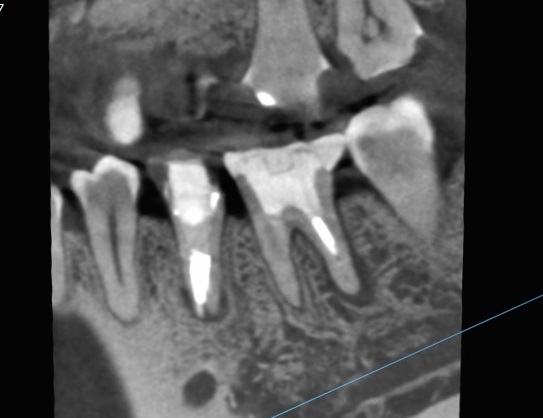

以前治療した歯の違和感。根管治療やり直し。30代女性。

• Before

After